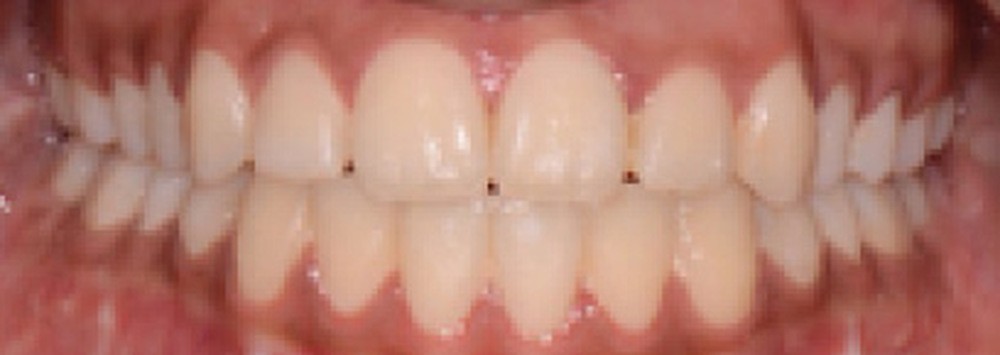

Le résultat de fin de traitement est satisfaisant. Le profil de la patiente est harmonisé. Une contention fixe mandibulaire et maxillaire de canine à canine est choisie.

La phase de préparation pré-chirurgicale a duré huit mois. La chirurgie a ensuite été reportée de trois mois par souhait de la patiente (départ en vacances puis volonté de réaliser la chirurgie durant des vacances scolaires). La phase de finition a été légèrement augmentée, du fait d’un mauvais port des élastiques de blocage par la patiente. Au total, le traitement a duré vingt-deux mois.